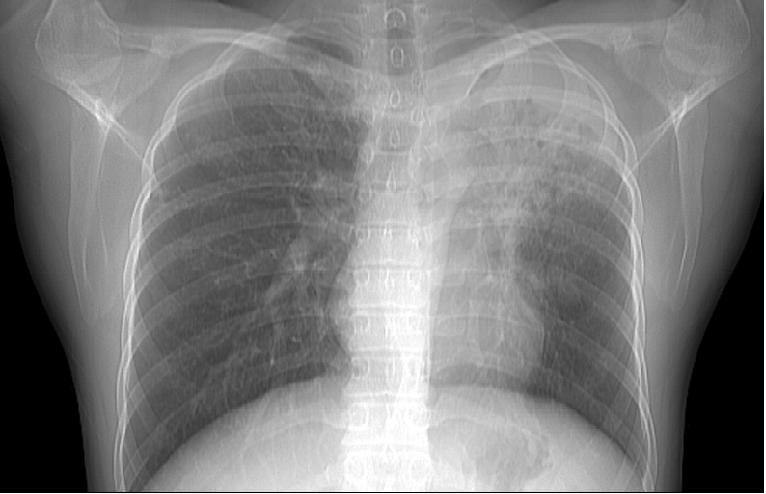

女,33岁,咳嗽5月。

首考:双上继发性肺结核(左上干酪病灶)。建议临床相关检查。

双上肺tb.伴左上胸膜增厚粘连

考虑双肺上叶继发性肺结核伴左侧上胸壁胸膜肥厚 粘连。